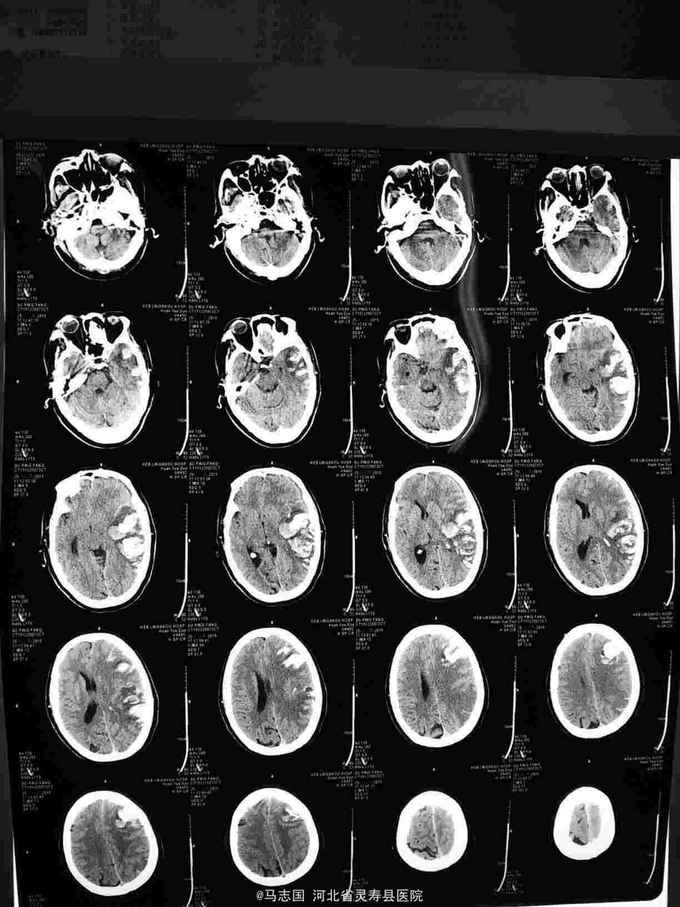

1. 晕厥待查?2. 高血压3级 极高危3.2型糖尿病,给你控制血压,稳定血糖,抗凝抑制血小板聚集,保护脑神经等治疗。入院5个小时后突然意识不清加重,伴恶心呕吐,双侧瞳孔不等大,急查头CT:左侧额顶大面积脑梗塞伴内广泛渗血及脑疝形成。紧急给予颅内血肿清除术,去骨瓣减压术。术后呼吸机辅助呼吸,脱水降颅压等治疗。

大面积脑梗死后,容易并发出血,早期CT未能显影,给予了低分子肝素钙及阿司匹林,大面积脑梗死病人早期还是不建议低分子肝素钙抗凝,尤其是在血压高的情况下,容易出血。